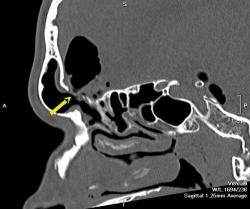

На снимках виден большой костный дефект (желтая стрелка) в задней стенке лобной пазухи, в полости черепа воздух, который прослеживается в области дефекта в полюсе лобной доли, в большой порэнцефалической кисте с уровнем жидкость-воздух (красные стрелки). Киста связана в передним рогом бокового желудочка, в противоположном желудочке и в третьем воздух (зеленые стрелки). На сагиттальных срезах виден воздух в мостовой цистерне вдоль ската. Поскольку дефект довольно большой, сейчас решается вопрос как лучше его закрыть эндоскопически или через трепанацию.